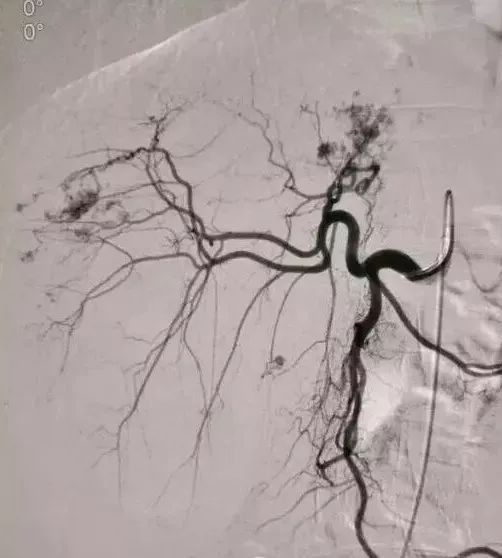

2、经导管血管栓塞法(Transcatheter embolization)

经原血管造影的导管或特制的导管,将栓塞物送至靶血管内,一是治疗内出血如外伤性脏器出血、溃疡病、肿瘤或原因未明的脏器出血。另一是用栓塞法治疗肿瘤,因肿瘤循环部分或全部被栓塞物阻断,以达控制肿瘤之生长,或作为手术切除的一种治疗手段;亦可用于非手术脏器切除,例如注射栓塞物质于脾动脉分支内,即部分性脾栓塞,以治疗脾功亢进,同时不影响脾脏的免疫功能。

常用的栓塞物质如自体血凝块、明胶海绵、无水酒精、聚乙烯醇、液体硅酮、不锈钢圈、金属或塑料小球及中药白芨等。